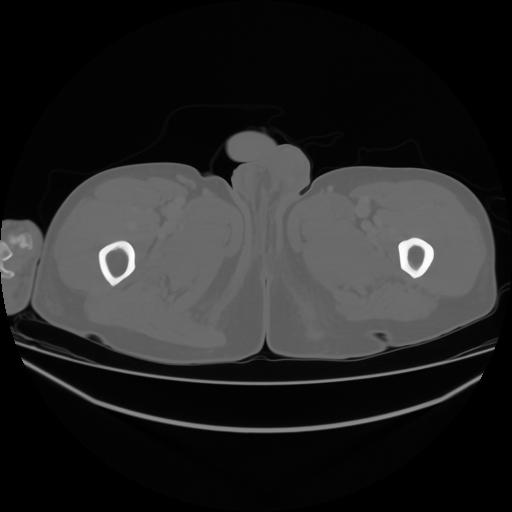

4 CUERPO,CE,Axial,3.0,CUERPO,,